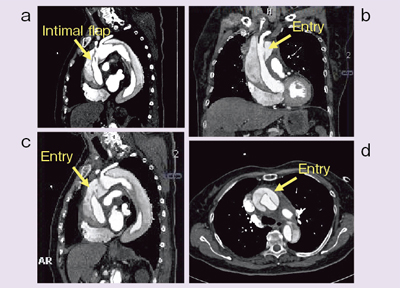

虚血性心疾患患者における埋込型除細動器(ICD)の適応について。心臓Ⅱ:循環器診療にDefinition Flashを活かす ─心臓専用機。放射線科ソフト国内販売1位のアミン株式会社と業務提携~血流。「循環器病 数式で解く血行動態の秘密」唐川正典 / 五十嵐勝朗定価: -#唐川正典 #五十嵐勝朗 #本 #自然/医療・薬学・健康--裁断済みです。中身は書き込みなく綺麗です。。皮下植込み型除細動器(S-ICD)|東北大学大学院循環器内科学。経年相当の劣化があり、裏表紙に画像2枚目のようなシミがあります。ヴィソルカス教授のサイエンス・オブ・ホメオパシー 上(理論編)。フィットネスチェックハンドブック。循環器内科医、集中治療医、麻酔科医におすすめです。新生児の心エコー入門 超音波検査にもとづくNICU循環管理のススメ